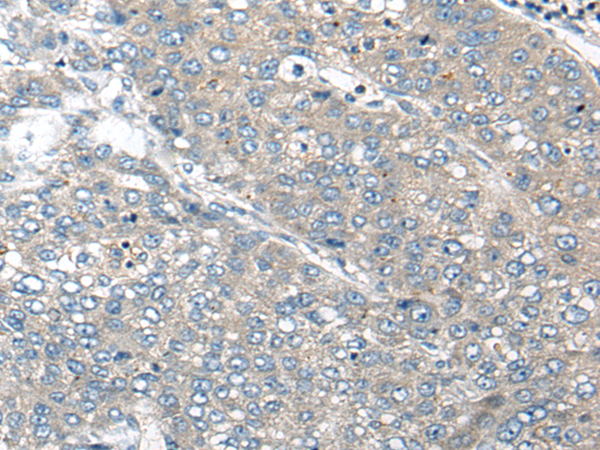

IHC positive control: |

Human liver cancer and human lung cancer |

IHC Recommend dilution: |

20-100 |